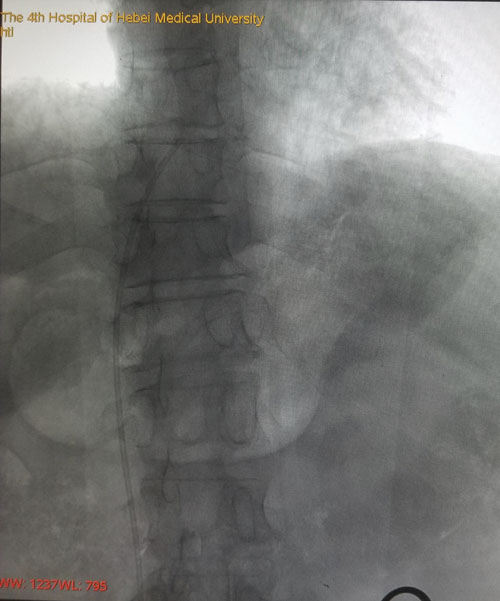

术前CTV评估股静脉及分支